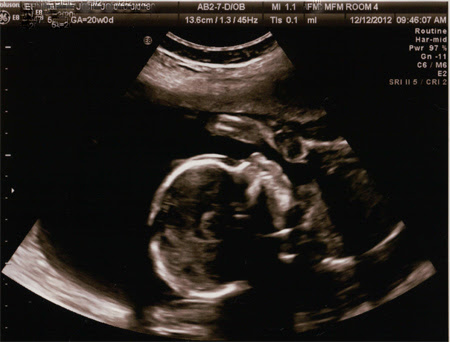

We found out today that we're having a BOY!

I don't think I'll ever get over how amazing that ultrasound is. The doctor even zoomed in so we could see the baby's mouth making sucking movements. He looks perfect.